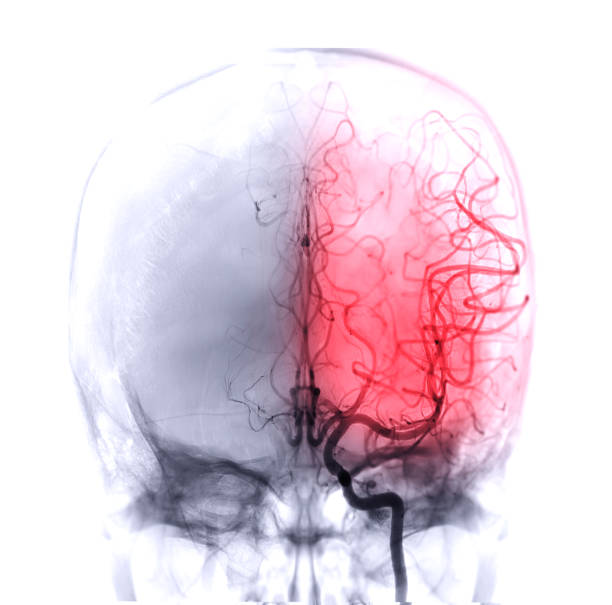

발작

뇌 혈액 공급이 감소하면 발작이 발생할 수 있습니다. 이러한 발작은 일반적으로 근육 경련과 같은 증상을 나타냅니다.

혼란

모야모야병 환자는 혼란 상태나 의식 소실 등의 증상을 겪을 수 있습니다. 이러한 혼란은 대개 뇌졸중과 관련이 있습니다.

말초 신경계 증상

모야모야병 환자는 얼굴, 팔, 다리 등의 미세한 움직임이나 감각 장애, 혹은 환각 등이 나타날 수 있습니다. 이러한 증상은 대개 반복적으로 나타납니다.